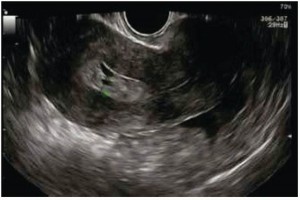

Diplomados en Ultrasonografía